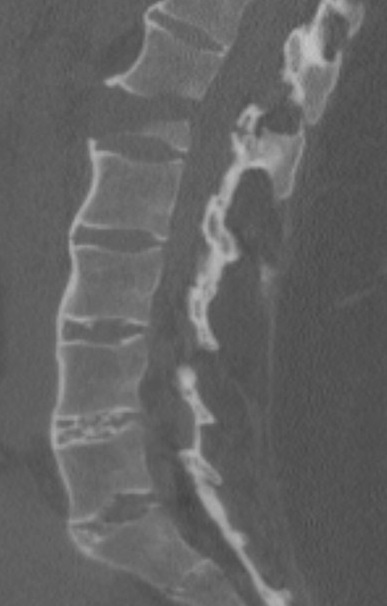

Aspect de fibrose , calcifiee du ligament

inter-epineuse posterieure et ligament para

vertebrale de L1-L5 en formation image de colonne de

bamboo ( bamboo spine ) |

Image radiologique TDM en

coupe sagital d'une spondilite -ankylosant de D12

-L5 avec image de fracture du L1 . Image de

osteophyte anterieure du D12 et L2 avec image de

fibrose du ligament paras vertebrale anterieuse etre

en vue très nette |